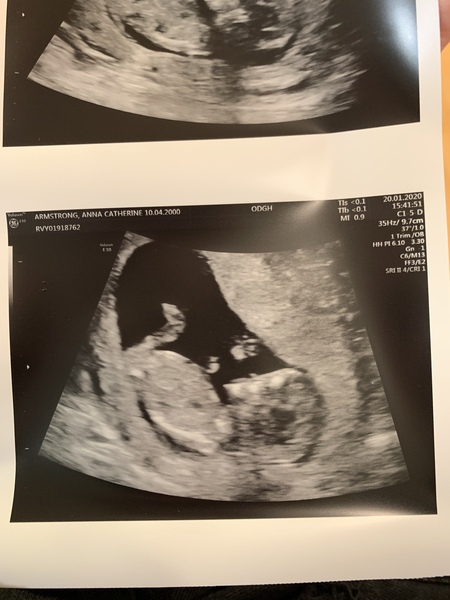

Firstmummytobe · 20/01/2020 20:51

Baby is fine!! Measuring 12 weeks 3 days, due date 31st July, so not actually having an august baby 🙈😂

If anybody can notice, babe was sucking it’s thumb on the scan😭😍❤️

Find out the gender on the 4th feb!!!

Omigosh @firstmummytobe that scan pic is amazing! A proper little baby!

Congratulations @Firstmummytobe what a gorge photo!